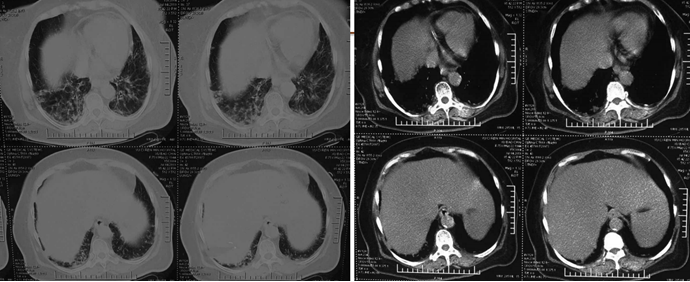

给予针对性抗感染治疗后,患者氧合指数逐渐升高,吸氧浓度逐渐下调,WBC基本正常,PCT逐渐下降。患者胸部CT较前明显改善(图6)

图6  患者治疗前后胸部CT比较

2. 临床表现及影像学